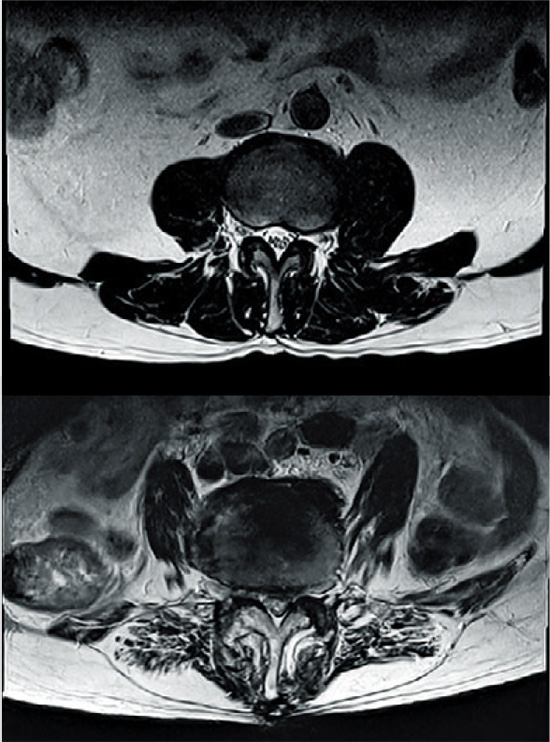

°Ç°­ÇÑ »ç¶÷ÀÇ Ç㸮 ±ÙÀ°(À§)°ú ±ÙÀ°ÀÇ Áö¹æÈ­°¡ ÀϾ Ç㸮 ±ÙÀ°(¾Æ·¡) MRI »çÁø. /Á¦ÀÏÁ¤Çü¿Ü°úº´¿ø Á¦°ø